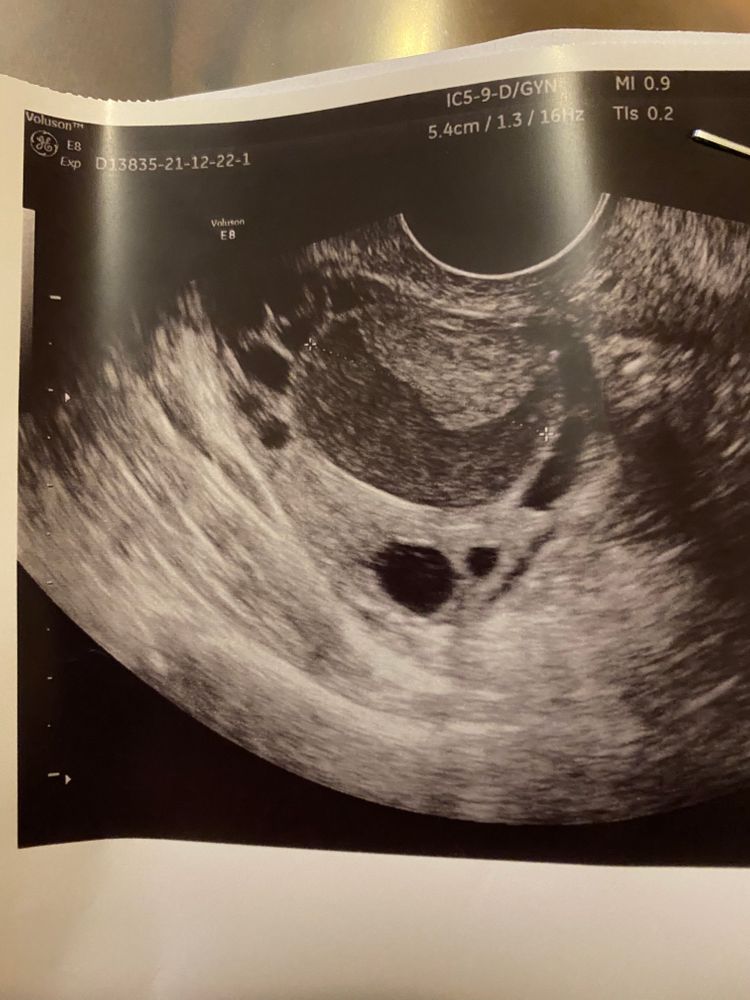

13 дц, врач сказала, что скорее всего киста жт и О была ночью. Но мне что то уже не верится. Жидкости не нашла. Киста 27 мм и какая то не такая, не похожа на кисту жт как в прошлом цикле

Не могла за ночь вымахать киста. Ни фолликулярная, ни, тем более, ЖТ. Либо с прошлого цикла, либо ДФ. И размер - это не киста. Ждите О сегодня-завтра.

В Ожидании Чуда, в прошлом цикле практически момент О поймали, в этом ДФ с яйценосным бугорком, тоже скоро лопнет. Я вижу так. Качество, конечно, хромает, но это не серое ЖТ со взвесью. Вам бы, конечно, прям сейчас ХГЧ уколоть хотя б 2-3 тыс ед, чтоб в кисту не ушёл, но оно не продаётся ни где давно(

Виктория Север, в прошлом цикле (последняя фотка) и жидкость была, поэтому сказали что О. А сегодня ни жидкости, и сразу киста с кровоизлиянием написали. Я думала доминантный фолликул должен быть немного темнее